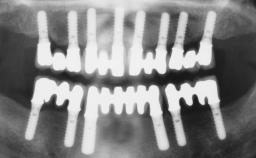

An 83-year-old male patient requested treatment for his existing maxillary complete overdenture and mandibular complete denture. He reported no general medical conditions of significance that would affect his dental treatment and was taking no prescription medication. He denied suffering from oral pain and displayed no evidence of parafunctional habits or temporomandibular joint disorder. Oral and radiographic evaluation revealed two retained maxillary teeth (13 and 15) supporting prefabricated ballshaped attachments. Both teeth were mobile and associated with active periodontal disease and extensive dental caries; these were considered non-restorable and were recommended for extraction. The patient’s existing complete maxillary and mandibular prostheses were approximately 2 years old. He was very satisfied with the appearance of both prostheses. His chief complaint was related to the instability and lack of retention associated with the existing mandibular prosthesis.

# of Implants | 2 |